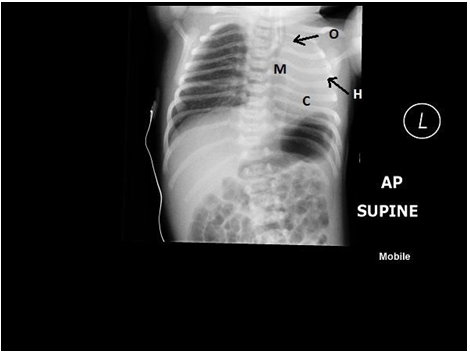

The first case we encountered was a 34 week preterm baby girl of 2 KG weight. The mother had polyhydramnios. Baby was frothing at mouth and a NGT failed to pass beyond 8 centimeters from anterior nares. The baby also had radial aplasia on the right side. A heart murmur was heard, confirmed later as a patent ductus arteriosus. A Chest X ray was ordered and this showed the NGT lying coiled in the upper pouch and a gasless abdomen; suggesting pure atresia without fistula. The right hemithorax was occupied by the heart shadow and there was a hyper inflated lug on the left side.

On the first day a laparotomy and gastrostomy was done. An esophagostomy was NOT done and the baby was kept on Replogyl tube low pressure continuous suction. Gastrostomy feeds were started on 3rd day. Further investigations confirmed an absent right lung with a rudimentary Rt bronchus and absent Rt pulmonary artery on both Echocardiogram and CT angiography. Right hypoplastic radius, grade 1 hydronephrosis due to PUJ obstruction and a patent ductus arteriosus were the other anomalies.

This was a term male baby, born with 2.9 KG weight. Ante natal scan at 36 week had shown evidence of polyhydramnios. Soon after birth, an NGT passed failed to pass into the stomach, confirming the diagnosis of esophageal atresia and the baby was shifted to NICU. A chest Xray was ordered on arrival in NICU and this showed hyperinflated Left lung with absent lung markings on the right side. The heart and mediastinum were grossly shifted to the right with a diagnosis of right lung agenesis, a contrast enhanced CT scan was done. This confirmed a Type 1 pulmonary agenesis with complete agenesis of Rt lung and Rt pulmonary artery and bronchus.